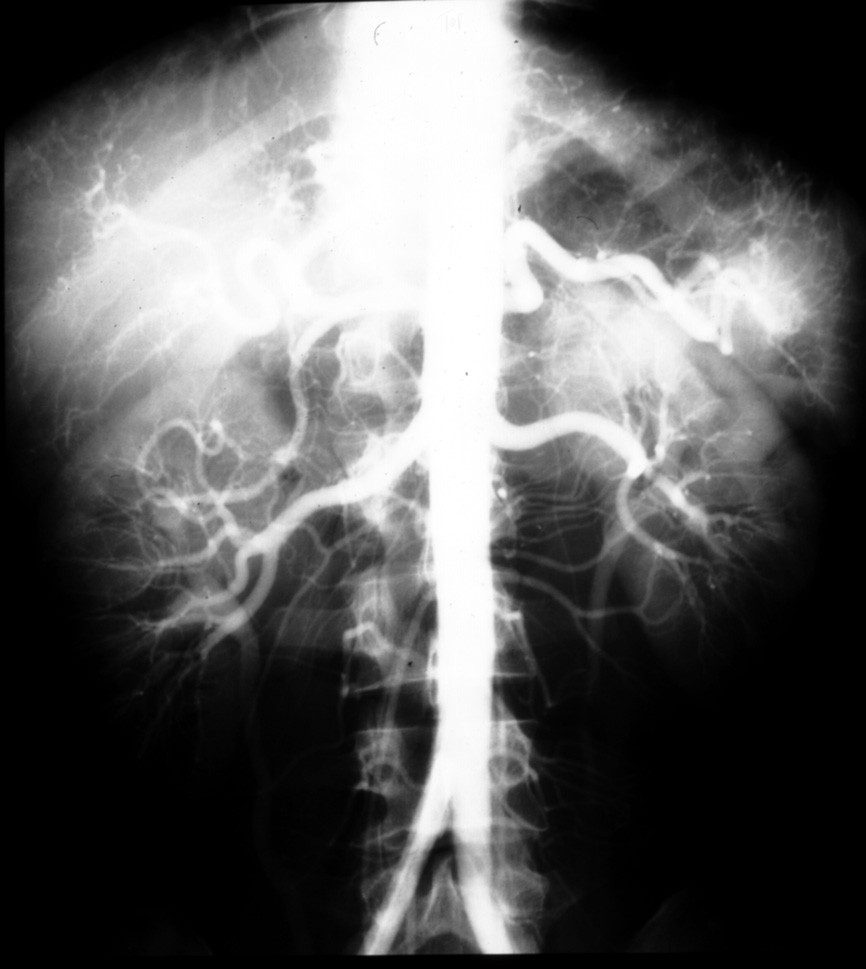

MS I 119 (AP) - Normal Aortogram - AP

Identify: main hepatic, gastroduodenal, splenic, hepatic proper,

right and left hepatic, right and left renal arteries